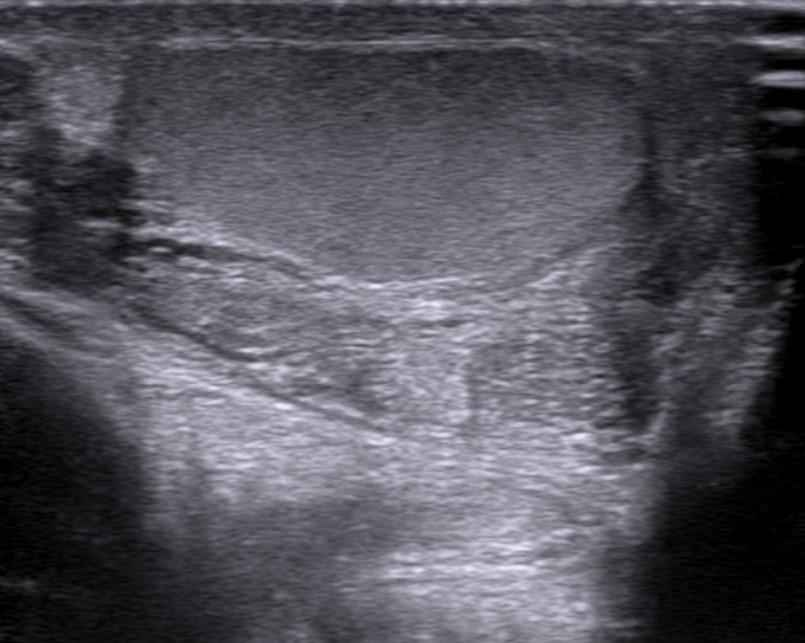

Case of the Week 31 2016 *33-year-old male with pain in left testicle. What is the most likely diagnosis? Answer Answer: Epididymitis Kategori:Cases Önceki yazı Case of the Week 6 2016 Sonraki yazı Case of the Week 17 2016